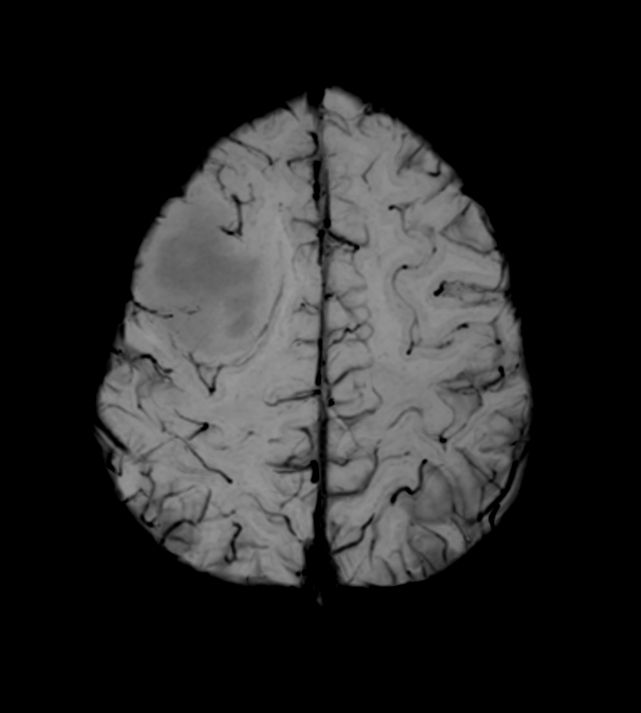

Diffusion (b1000)